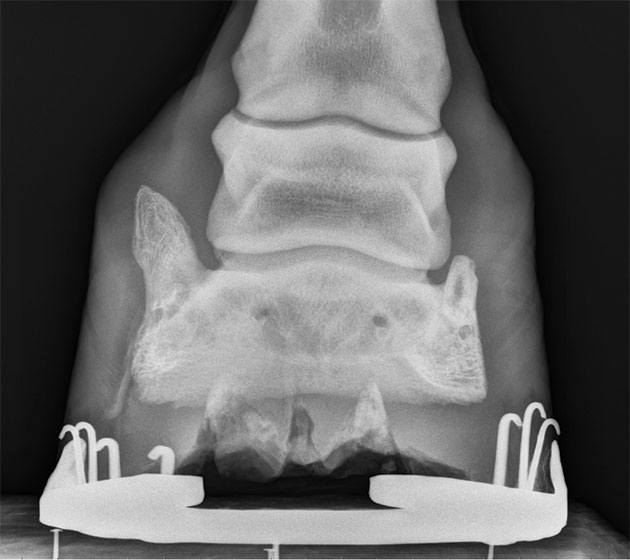

While most horses don’t exhibit lameness with sidebone, it is easily spotted and looks alarming on an X-ray. “In general, for most horses, it’s not a source of lameness,” says Dr. Durham. “It gets blamed a lot of times because it’s there and easy to see radiographically, but often it’s an incidental finding.” The boney protrusions can also be felt by palpating on the outside of the pastern, and severe cases may even be sensitive to touch. Horse owners are usually in shock when seeing them so plainly on the X-ray because their horses are generally showing no signs of being sore. “Even if the horse is limping, and we know that sidebone is present radiographically,” Dr. Durham says, “I’m usually looking for something else because it’s uncommon for that to be the cause.” One of those potential problems is an injury to the collateral ligament of the coffin joint that stabilizes both sides. This injury has been correlated with the presence of sidebone. For this reason, medial- lateral balance of the hoof is a critical issue in affected horses.

The main sidebone risk factor is that this fine bone is very sensitive. If and when a horse hits this bone on something, it can be extremely painful like stubbing your small toe on the edge of a wall. A horse may limp severely for a few days until the inflammation calms down. This bone also has a higher risk of being fractured because of its frailty and location. The challenge is that these breakages can be very hard to detect because they are so small. “Fractures of sidebone are actually quite painful when they happen,” Dr. Durham says. “They usually resolve fairly well, but sometimes some instability in the area can keep them somewhat sore.” Another concern with sidebone is when it grows into other spaces. “One of the things that can cause a problem with sidebone is if it grows inward toward the short pastern bone, then it can potentially impinge on some of those other tissues, and that can be very painful,” he adds. Fortunately, this is only seen in very severe cases.